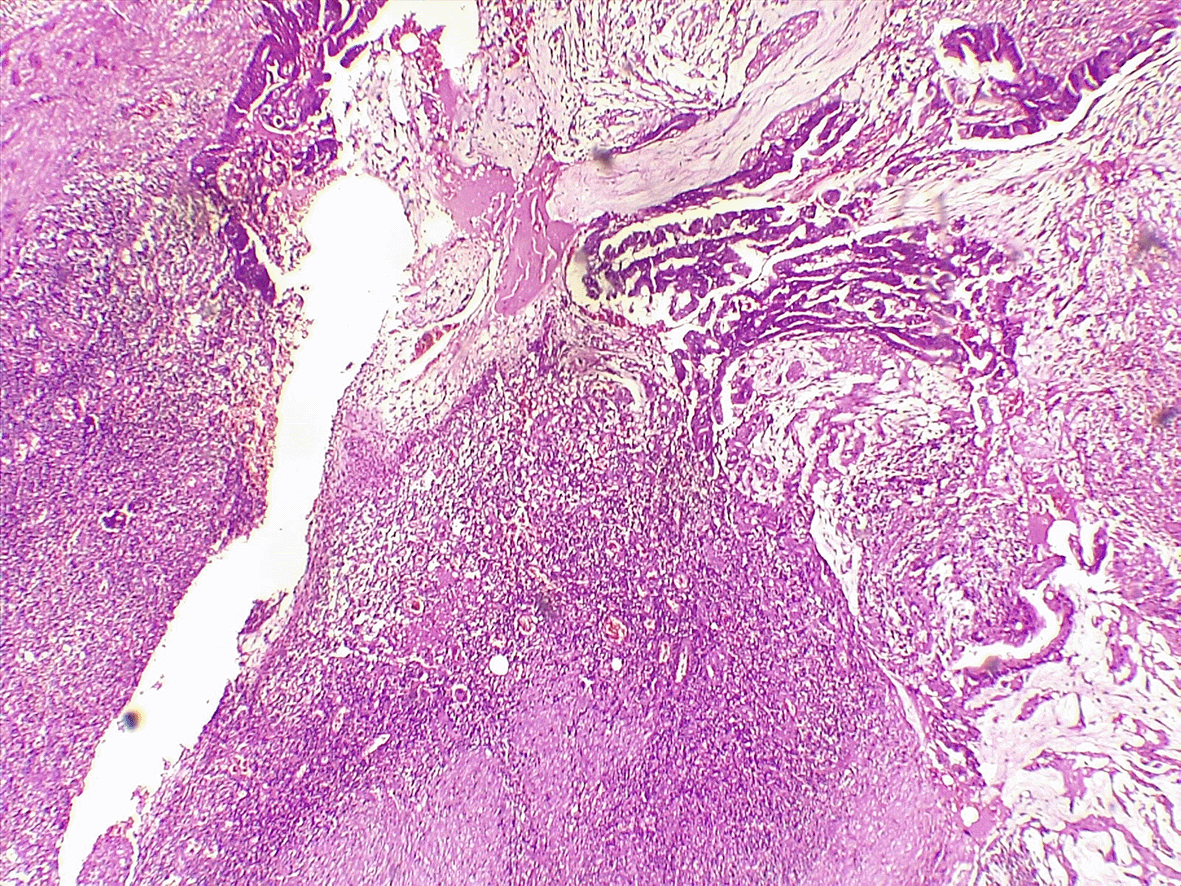

An 81-year-old woman with a history of diabetes mellitus, hypertension, arterial fibrillation, and ventral hernia repair was scheduled to undergo surgery for a recurrent hernia. She consulted an emergency department for rapidly increasing abdominal pain for 6 days. Upon examination, the umbilicus bulged with overlying sphacelous skin (Figure 1). Biology was as following: CRP = 167.3 mg/L, WBC = 12020/mm3, creatinine = 121.84 μmol/L, urea 9 mmol/L, hemoglobin = 12.3 g/dL. An abdominal CT scan revealed a herniated right colon through a 25 mm defect, an enlarged appendix measuring 18 mm, and communication with a 5 cm intrasaccular abscess (Figure 2). She then rushed to the operating theater. Upon incision, pus was evacuated from the hernial sac. The right colon was incarcerated within the aponeurotic defect, with no signs of digestive distress, and the peritoneal cavity was not contaminated due to the constriction ring at the neck of the sac. The appendix was gangrenous with a perforated tip eliciting mucus (Figure 3). Thorough lavage with appendicectomy and herniorrhaphy was performed. She died on 5th postoperative day to a pulmonary oedema. Histological analysis revealed a well-differentiated adenocarcinoma that developed within a serrated adenoma (Figure 4). It was classified pT3. Mucus was acellular (Figure 5). The hernial sac harbors similar cancerous cells.